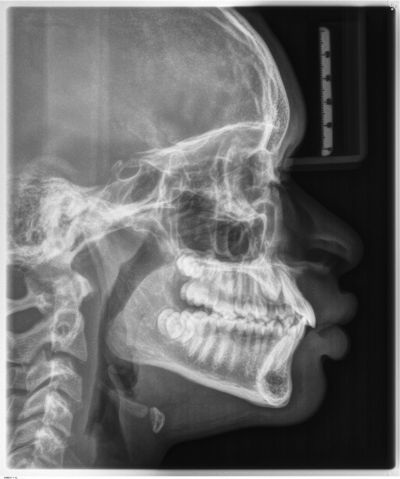

One case posted to the community involved a 13-year-old with a lingually displaced UL3 and plans for full braces, extraction of the primary ULc, and possible exposure and ligation (Figs. 1–5). The treating orthodontist asked: How likely is this canine to correct on its own after extraction?

Fig. 4